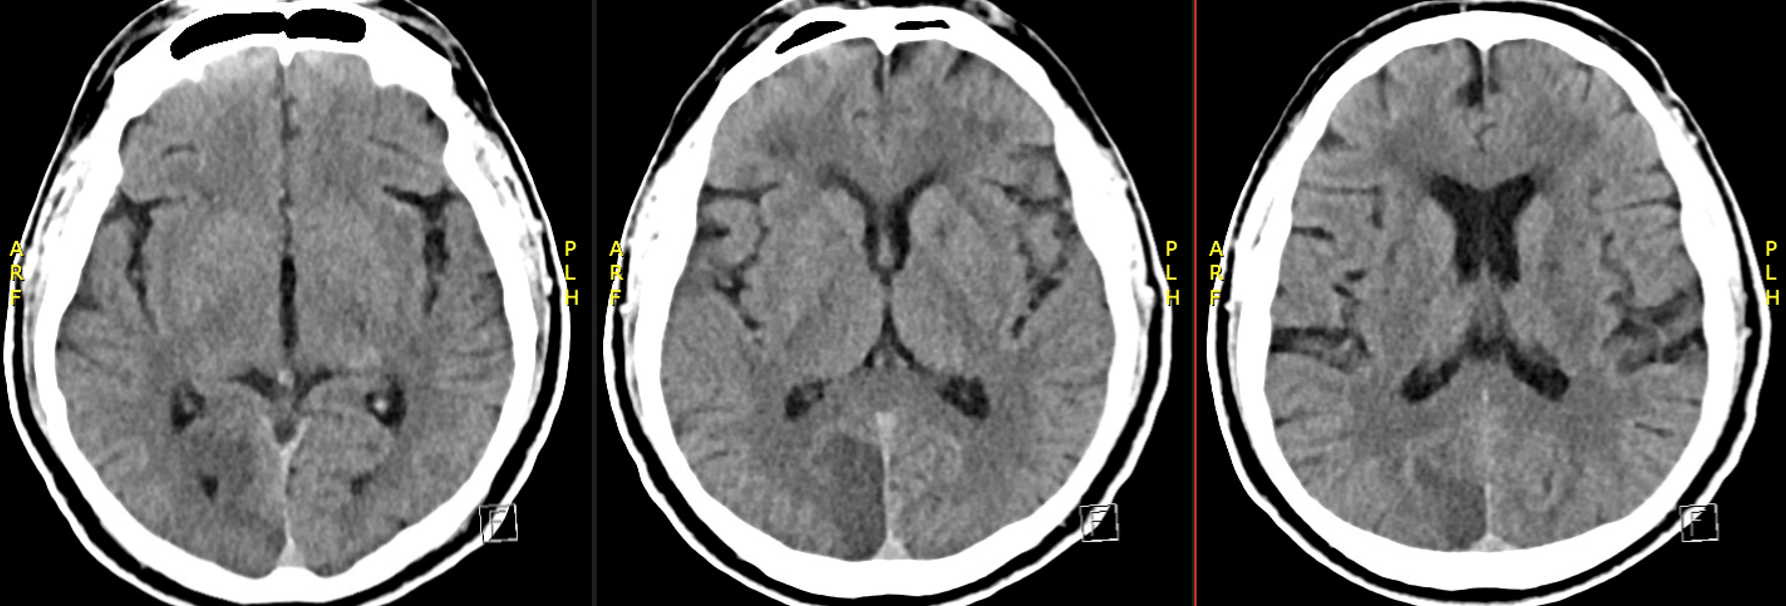

Another great vasa vasorum case from Guglielmo Pero, MD